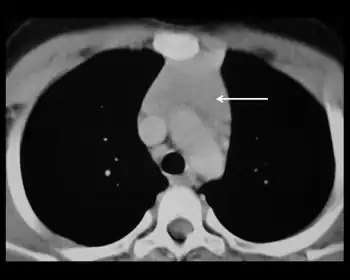

| Thymic hyperplasia | |

Thymus hyperplasia refers to an enlargement ("hyperplasia") of the thymus.[1]

It can be associated with myasthenia gravis.[2][3] Magnetic Resonance Imaging can be used to distinguish it from thymoma.[4]